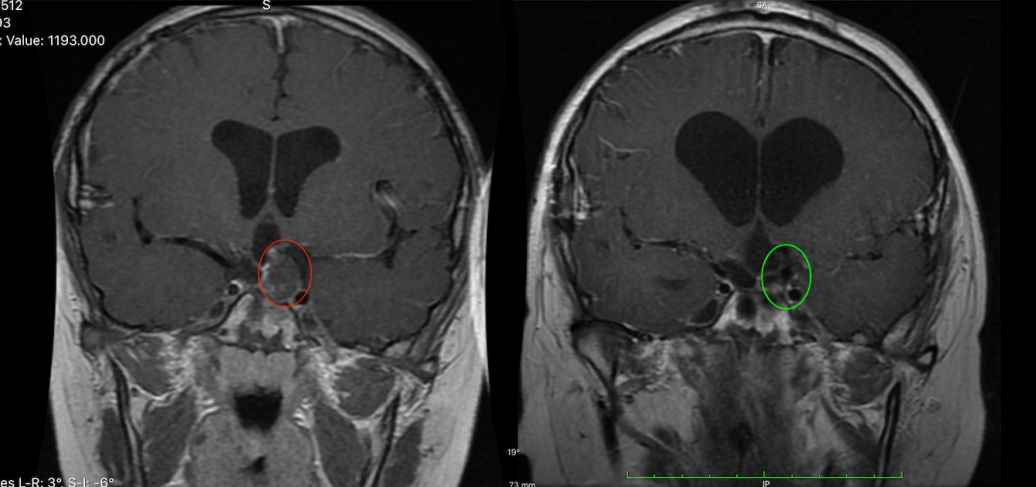

1.33岁周老师,中脑背侧胶质瘤

33岁的周老师因头部不适和眼部肿痛就医,检查结果显示中脑背侧占位,提示低级别胶质瘤可能,并被告知病变位置疑难,无手术机会..……周老师为求一线生机,远程咨询INC德国巴特朗菲教授,教授凭借高超技巧为其顺利全切病变,如今的周老师恢复良好,对巴教授和INC心怀感恩。

中脑背侧胶质瘤

“我去了中国较好的医院,也找了中国乃至较好的医生,假如我在国内做手术的话,那么要么就是致残,致残率比较高;要么就是下肢瘫痪,要么就是嘴歪眼斜的;生活质量不好。在网上无意中发现了上海INC国际神经外科,之后我就决定跟她们沟通联系。这才知道还有国外治疗这一个门路。让我重见光明,较终我决定去找德国的巴特朗菲教授去做手术。对治疗结果相当满意,巴教授治疗后,我回到云南,去了医院复查,医生都说我这是一个奇迹。在他们看来是不可能完成的任务,但是巴特朗菲教授确实完成了。医疗技术无国界,如果确定在中国无法做手术的时候,我想把更好的目光转向欧洲,转向巴特朗菲教授。因为那里可能有人给你开启重生之门!”——周老师。